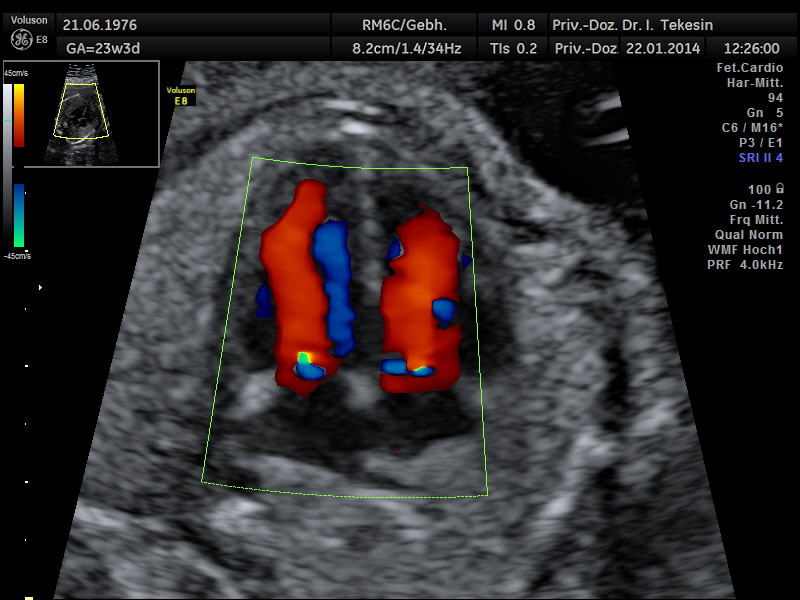

Normaler Vierkammer-Blick mit Farbe